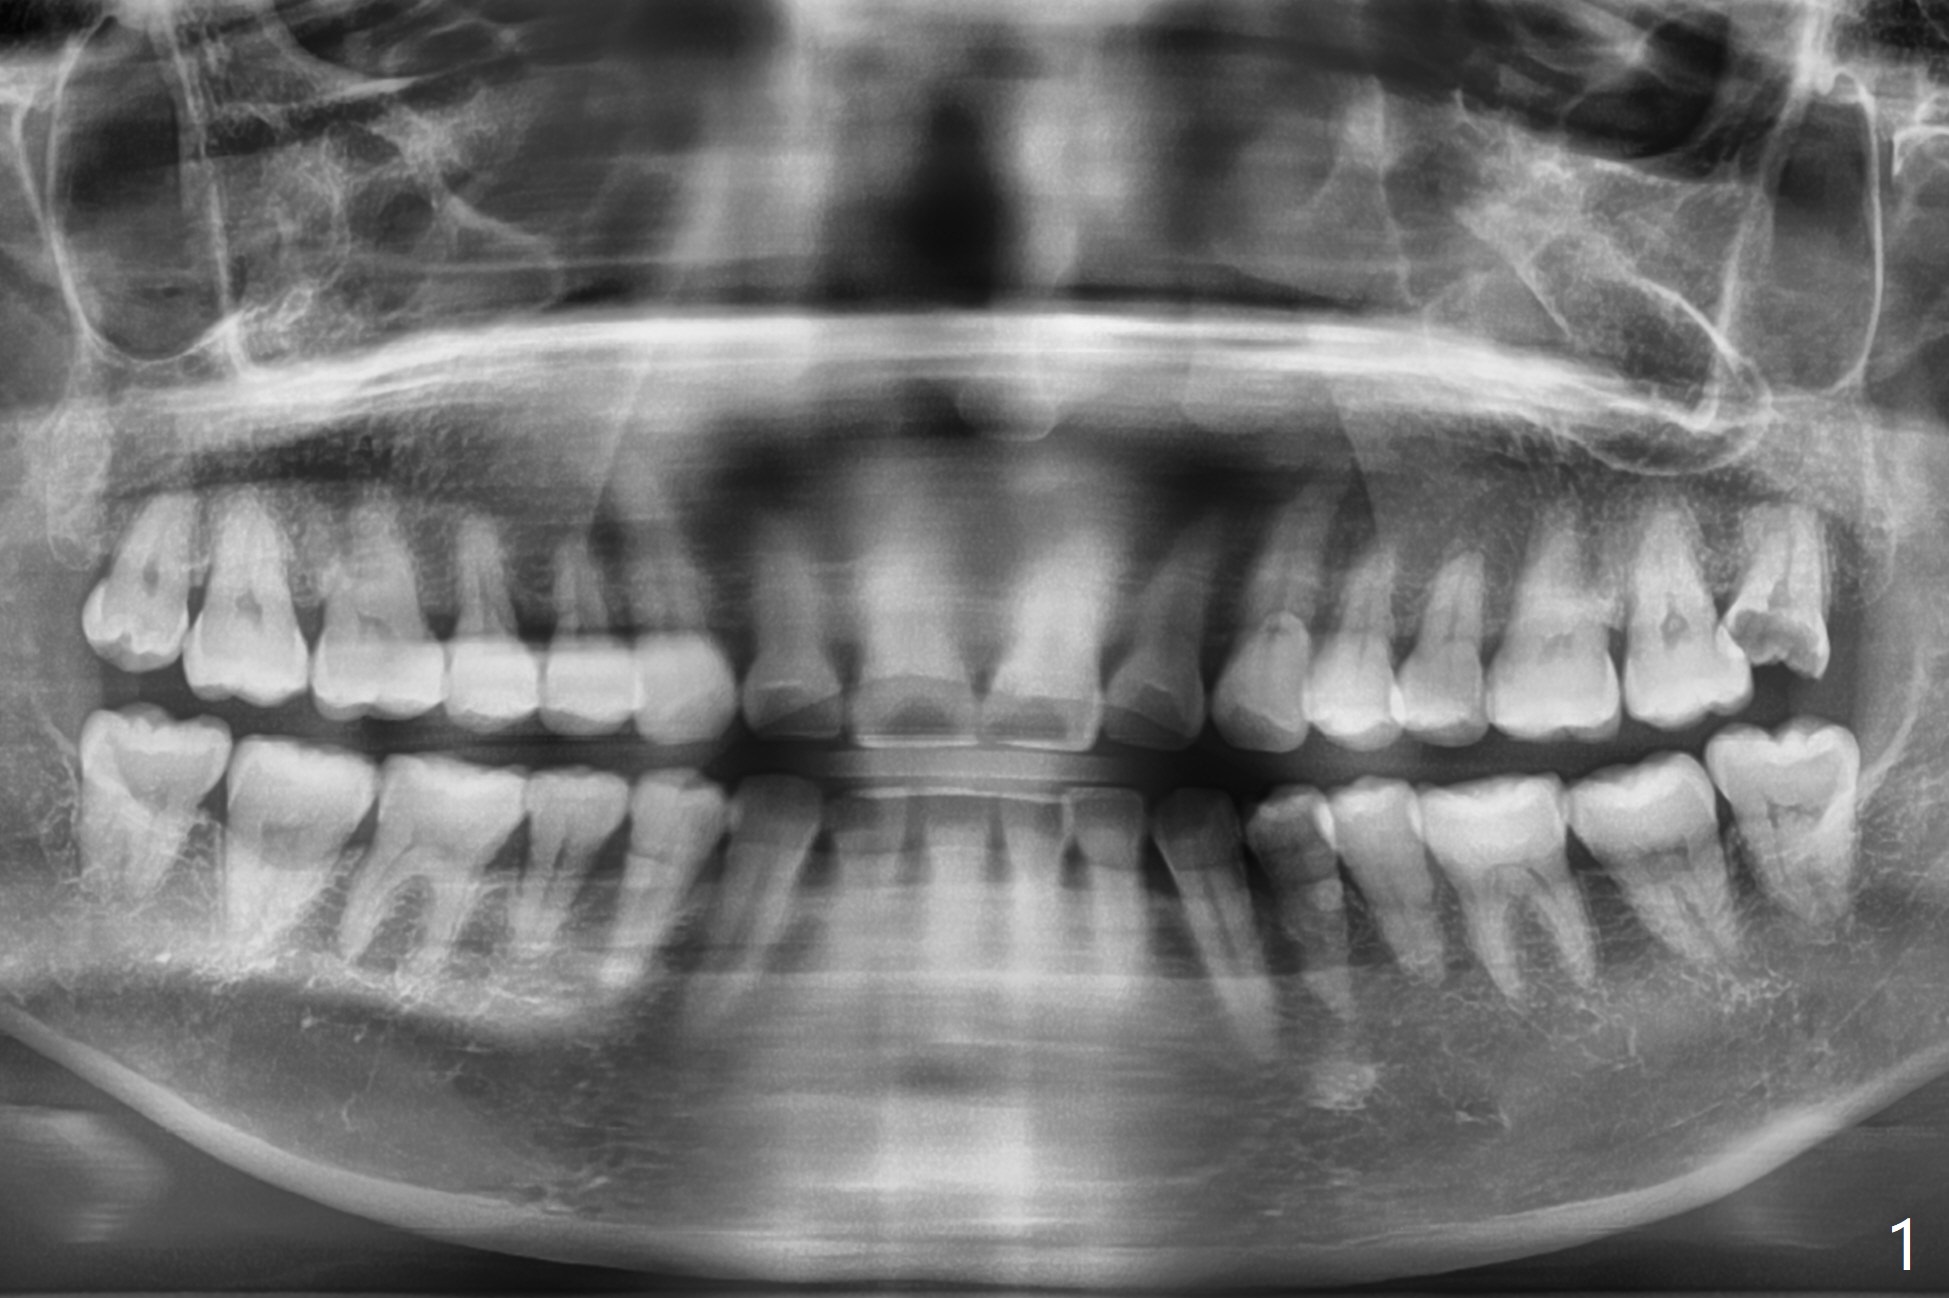

A 48-year-old woman requests extraction of 4 of the 3rd molars because of cheek bite, especially the left (Fig.1). The lower molars are buccal in position, while the upper one buccoversion. Following extraction, no split is emphasized to prevent dry socket. Elevator is placed freely mesiobuccal to the 3rd molar for breakdown of pdl since there is ample bone between it and the 2nd molar, in contrast to the other case.